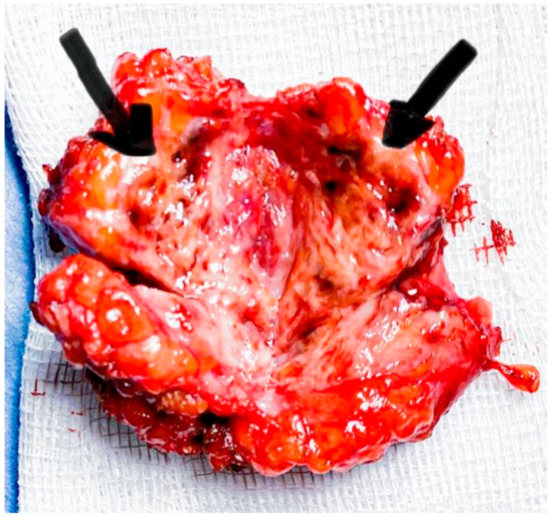

2.1. Case 1

2.2. Case 2